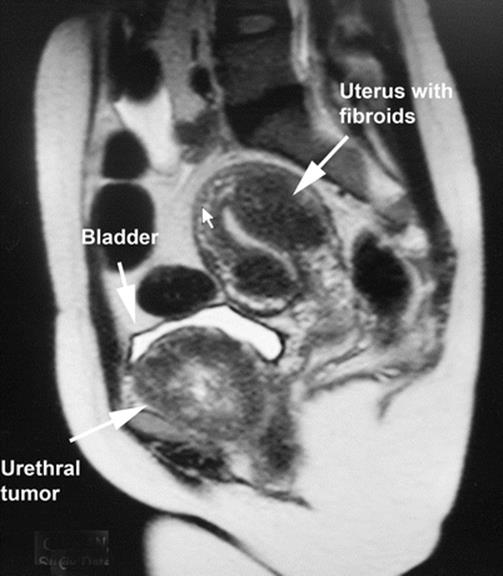

8.13 Large Urethral Leiomyoma Causing Urethral Obstruction

During her second pregnancy, the young patient in Figs. 8.43, 8.44, 8.45, 8.46, 8.47, 8.48, 8.49, 8.50, 8.51, 8.52, 8.53, 8.54, 8.55, 8.56, 8.57, and 8.58 presented with difficulty in voiding, tenderness in the anterior vaginal wall, and the feeling of a mass. Physical examination revealed a large, nontender, elastic, nonmobile mass inferior to the pubic bone. The mass displaced the urethra inferiorly.

Sagittal T2 MRI of the midpelvis reveals a large mass, mostly solid, with areas of necrosis and fluid displacing the anterior vagina and urethra inferiorly. The uterus is normal except for several small fibroids, and the adnexa are normal

Fig. 8.44

An axial MRI shows the replacement and displacement of the urethra by the large mass. Multiple areas of necrosis are seen. The arrows outline the tumor